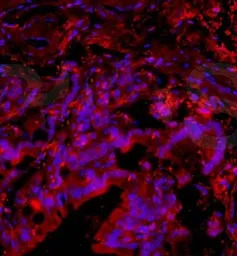

IHC-Fr analysis of rat brain tissue using GTX37576 PACAP antibody.